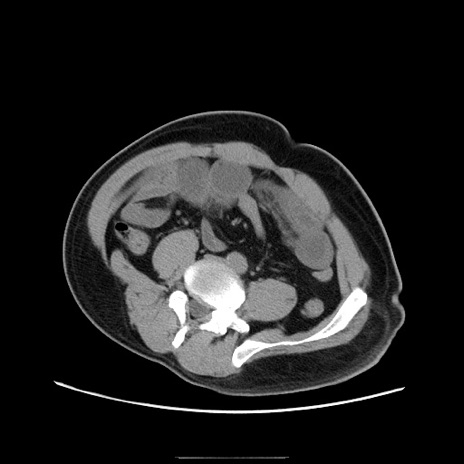

冠状断像